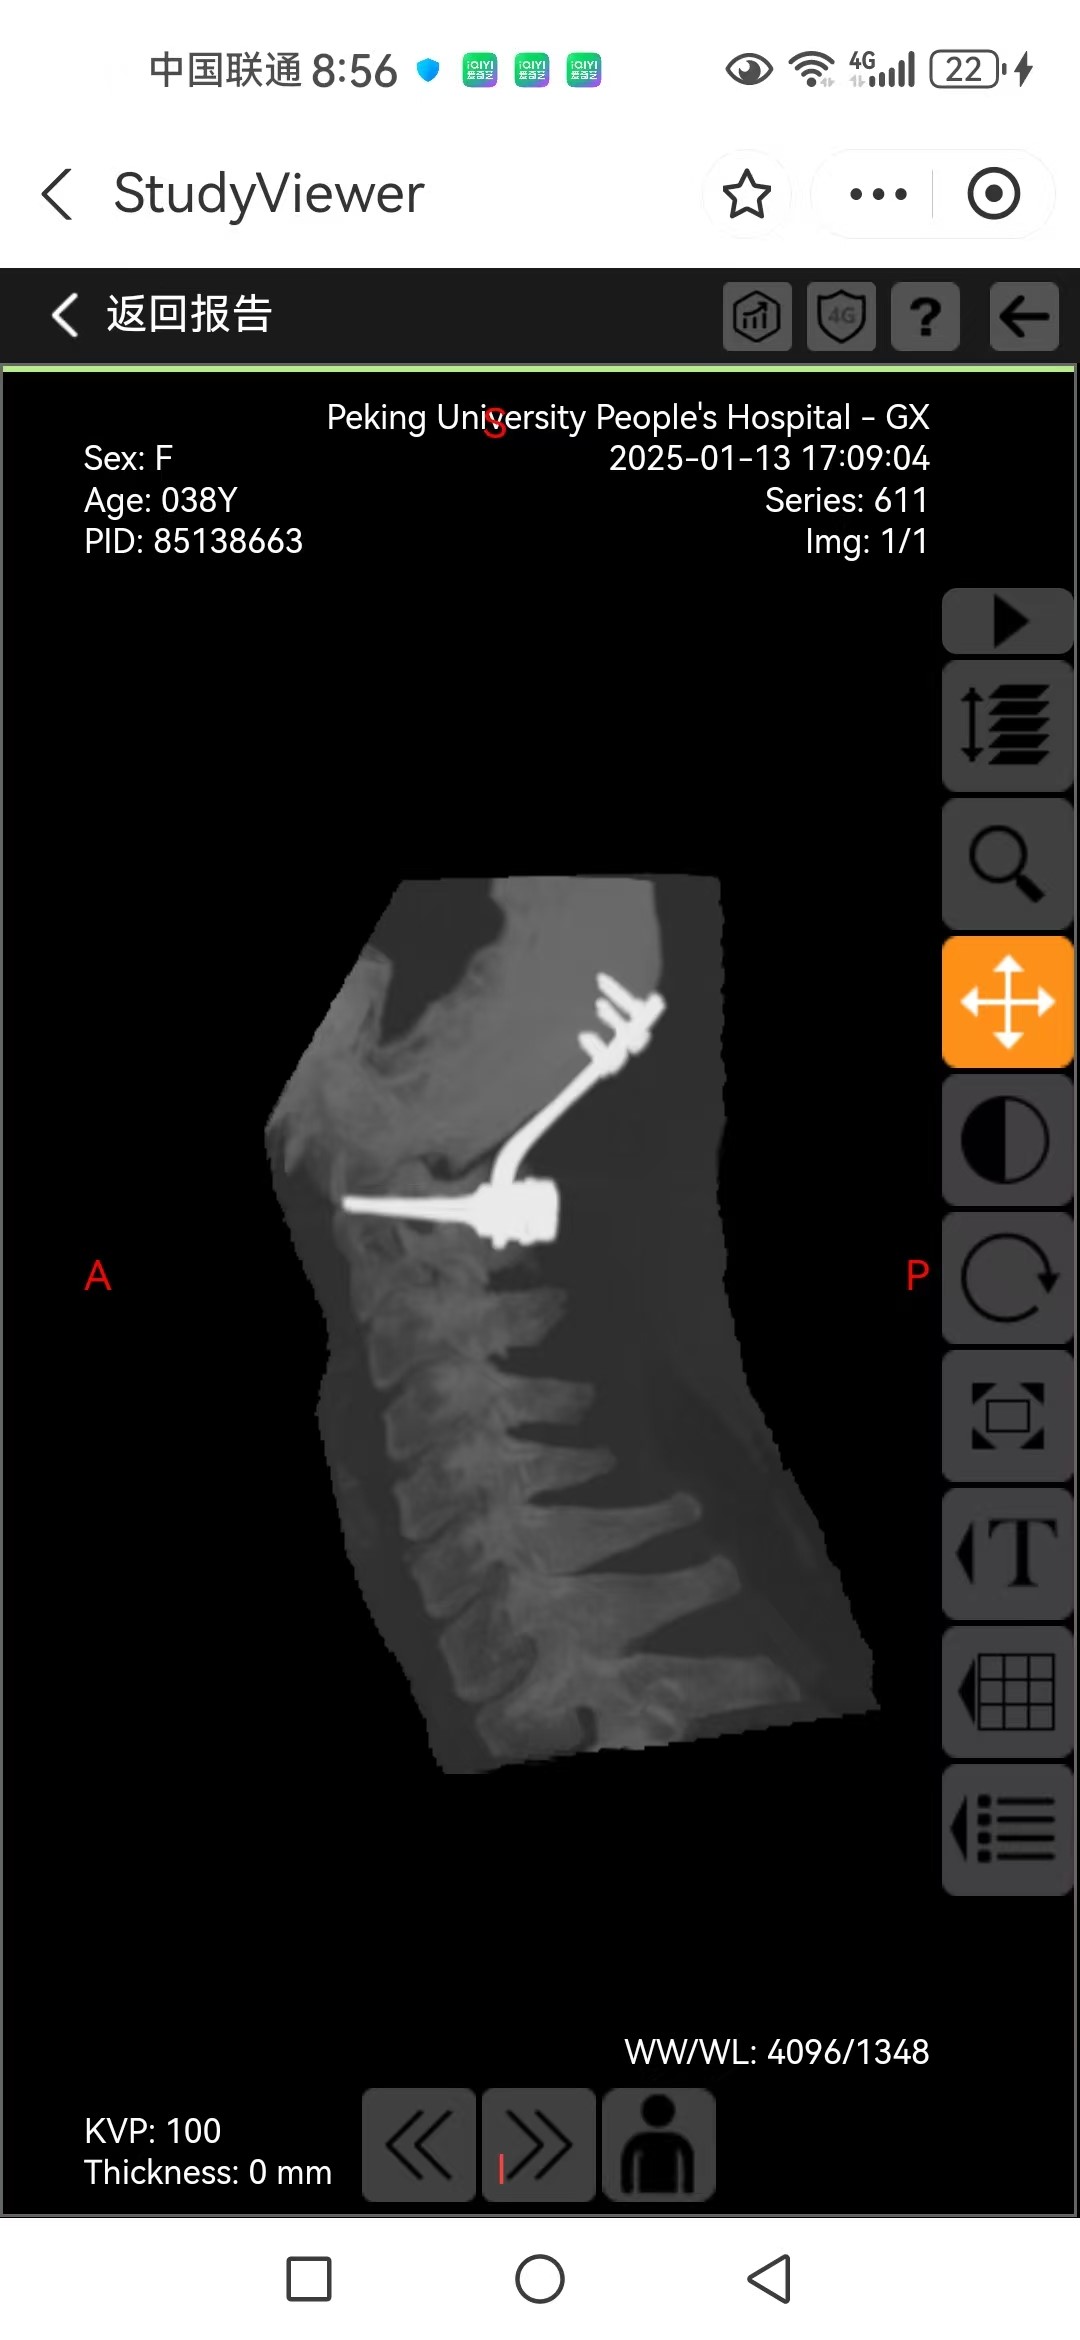

• 日期:2025.01.09

• 医院:人民医院

• 主刀:王超

• 术后影像: